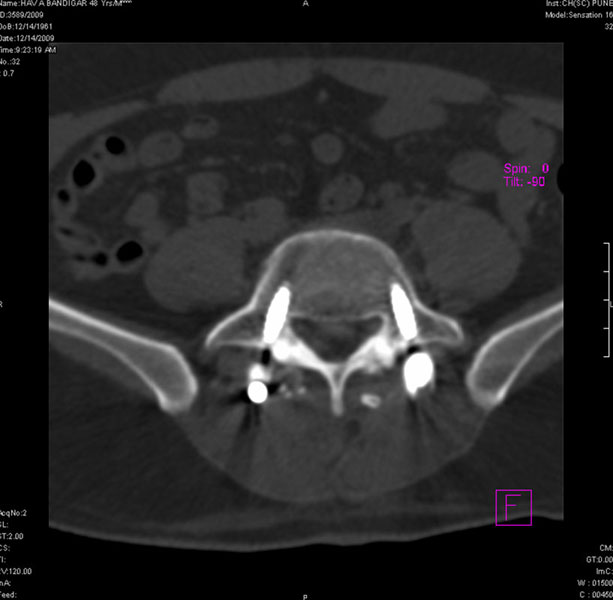

Spondylolisthesis malformations

Spondylolisthesis implies slippage of one lumbar vertebra over the next one, causing pain and nerve compression. Patient can also have difficulty in walking and numbness of the legs. Usually these patients need evaluation lumbar spine by MRI and CT scan, followed by spinal instrumentation and fusion.